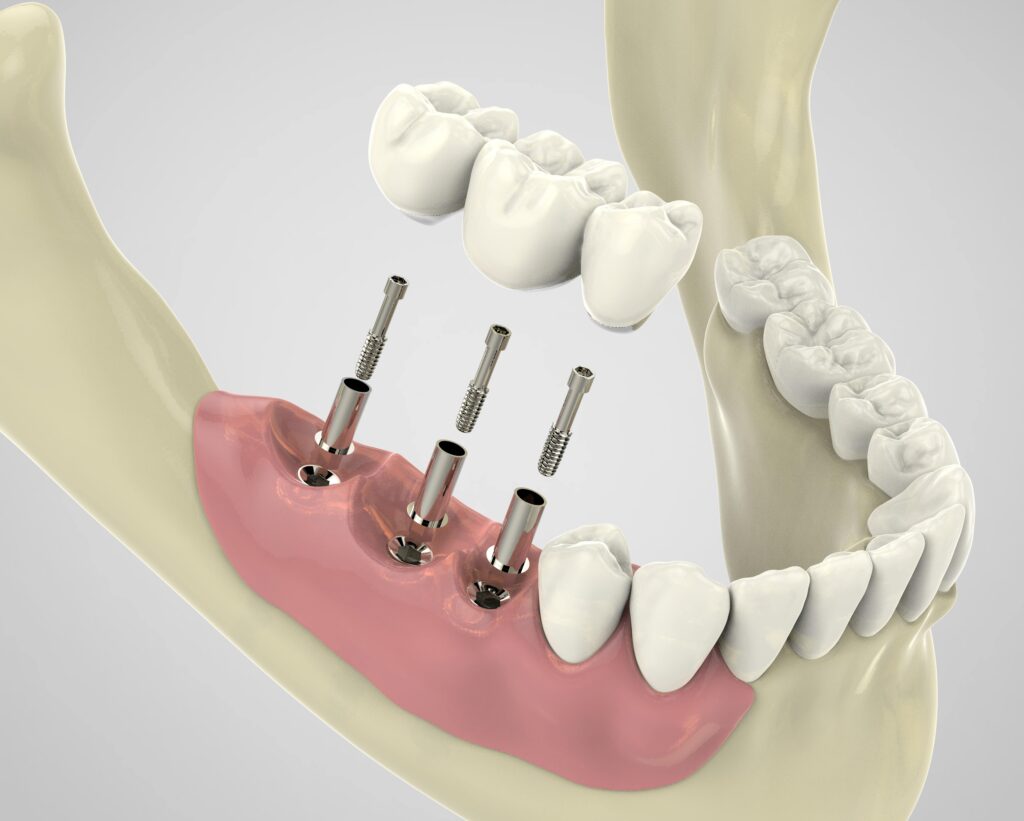

Dental implants are a state-of-the-art solution for replacing missing teeth, designed to replicate the structure and function of natural teeth closely. They consist of three key components: the implant itself, the abutment, and the crown.

The implant is a small titanium post that serves as a synthetic tooth root. It is surgically placed into the jawbone, where it integrates with the bone tissue through a process called osseointegration. This integration provides a stable and durable foundation for the replacement tooth.

Atop the implant, an abutment is attached, which acts as a connector between the implant and the final restoration. The abutment protrudes slightly above the gum line, providing a base for the crown, which is the visible part of the dental implant.

The crown is custom-made to match the color, shape, and size of the patient’s natural teeth, ensuring a seamless blend with the surrounding dentition. It is typically made from porcelain or ceramic materials, known for their strength and aesthetic appeal.

The process of getting a dental implant can span several months, starting from the surgical placement of the titanium post in the jawbone to the fitting and adjustment of the crown. Despite the time commitment, the result is a highly functional and aesthetically pleasing tooth replacement that feels and looks like a natural tooth.